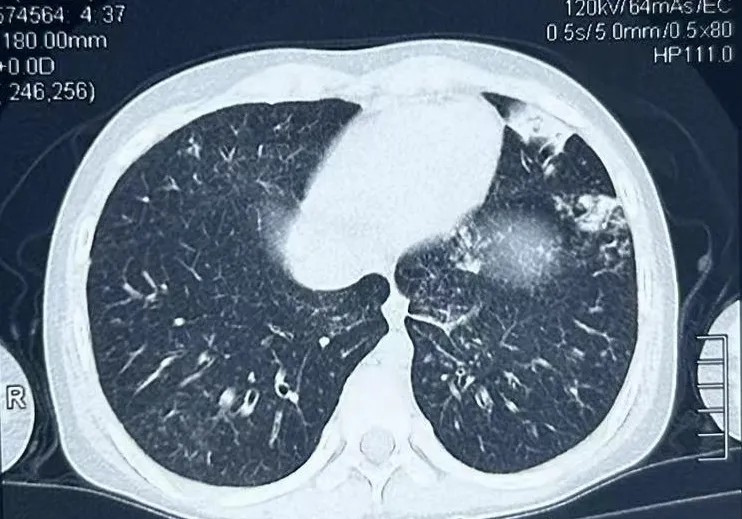

患儿术前胸部CT检查

小学六年级的王同学(化名)4个月前受凉后出现发热、咳嗽、咳痰,外院完善胸部CT诊断“肺炎”,先后予“头孢、阿奇霉素”抗感染治疗后体温恢复正常。2个月余前上述症状再发,就诊于当地儿童医院,再次予“头孢、阿奇霉素”抗感染治疗后体温恢复正常。2周前患儿无明显诱因再次出现发热,体温达39.2℃,伴气促,外院完善胸部CT提示肺部炎症较2个月前进展,再次予“头孢、阿奇霉素”抗感染治疗。10天前体温恢复正常,仍有反复咳嗽、咳脓痰。

手术定于7月1日上午8点半,由呼吸与危重症医学科主治医师对患儿进行电子支气管镜肺泡灌洗诊疗术,气管镜室内上级医师进行现场指导,在麻醉科副主任医师张本厚、芦海燕及内镜室护理助手的密切配合下顺利开展,电子气管镜经患儿自然气道进入肺部,其左右主支气管、各叶段气管支气管均可见较多脓性分泌物,充分吸引后,于左肺下叶外基底段、右肺下叶外基底段、左肺舌叶进行灌洗,时间仅为10分钟左右,全程心电监护严密观察患儿心率、血氧饱和度,治疗结束后患儿很快苏醒,10分钟左右即离开苏醒室。7月2日肺泡灌洗液检查回报白色念珠菌、黄曲霉、化脓性链球菌、巨细胞病毒感染,眼科杜葵芳主任完善眼底检查考虑患儿同时合并CMVR,遂予伏立康唑、头孢曲松、更昔洛韦联合抗真菌、抗细菌、抗病毒治疗。